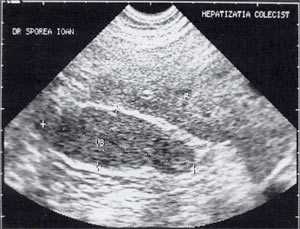

Материалы и методы

В исследовании, проведенном в США, "желчный сладж" выглядел в виде гиперэхогенного образования в желчном пузыре с горизонтальным уровнем без задней тени, форма которого медленно изменялась при движении больного [10]. Характерный признак "желчного сладжа" - изменение его вида на сканограмме в зависимости от изменения положения тела больного и медленным достижением нового горизонтального уровеня. Общим правилом является отсутствие дистальной акустической тени. Эхогенность сладжа может быть различной. Иногда сладж заполняет весь желчный пузырь, затрудняя дифференцировку между тканью печени и желчным пузырем. Эта ситуация называется "гепатизация желчного пузыря" (рис. 1).

Рис. 1. Гепатизация желчного пузыря, полностью заполненного сладжем.